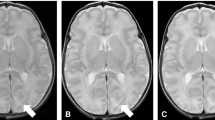

Accelerated MPRAGE reduced scan times by 38% compared to C-MPRAGE (142 s vs. 320 s). For quantitative error metrics, DNN showed better performance than GRAPPA and E-SPIRIT (p < 0.001). For qualitative evaluation, overall image quality of DNN-MPRAGE was comparable (p > 0.999) or better (p = 0.025) than C-MPRAGE, depending on the reader. Pixelation was reduced in DNN-MPRAGE (p < 0.001). Other qualitative parameters were comparable (p > 0.05). Lesions in C-MPRAGE and DNN-MPRAGE showed good agreement for the dice similarity coefficient (= 0.68) and linear regression (R2 = 0.97; p < 0.001).

• DNN-MPRAGE outperformed conventional reconstruction on accelerated scans (SSIM of DNN-MPRAGE = 0.96, GRAPPA = 0.43, E-SPIRIT = 0.88; p < 0.001).

• Compared to C-MPRAGE scans, DNN-MPRAGE showed improved mean scores for overall image quality (2.46 vs. 2.52; p < 0.001) or comparable perceived SNR (2.56 vs. 2.58; p = 0.08).